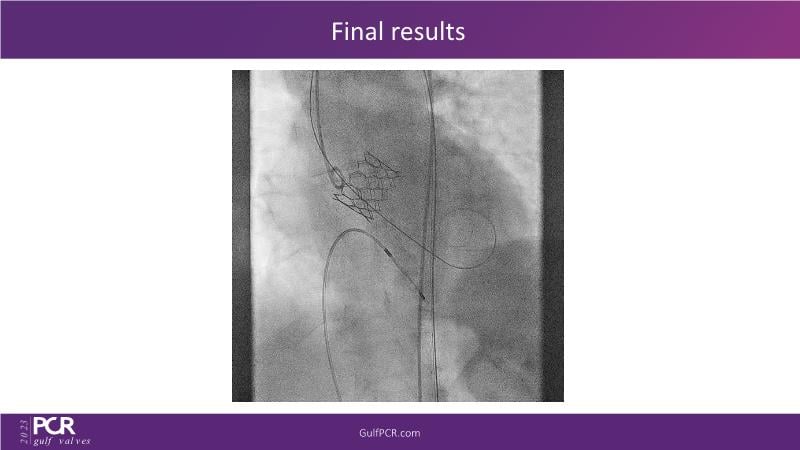

Essentials of lifetime management of TAVR patients using novel Myval THV

Join this GulfPCR-GIM 2023 session to explore the Myval next-generation THV technology, uncovering its unique features, procedural advantages, and clinical benefits, from extensive patient data. Learn also about the CorAlign technique that ensures precise commissural and coronary alignment while preserving coronary access, and gain insights into the precise sizing, positioning, and deployment techniques for the Myval THV.

- To understand the technique of precise sizing, positioning and deployment of Myval THV